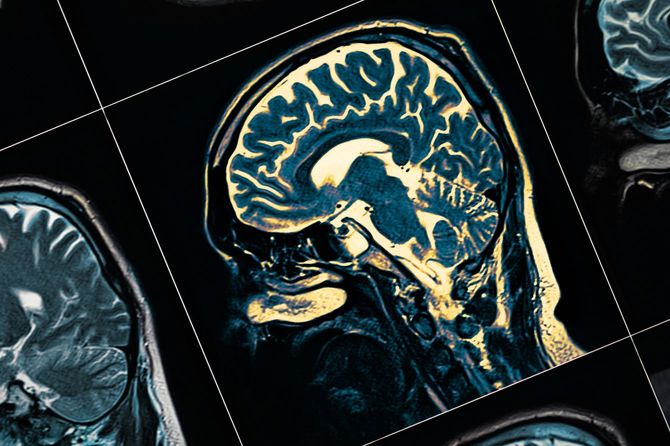

健診から4日後、河津さんと妻は近くの大学病院を受診し、さまざまな検査を受ける。

その約2週間後、妻はアルツハイマー型若年性認知症と診断。その月のうちに河津さんは、妻の自立支援医療を申請した。